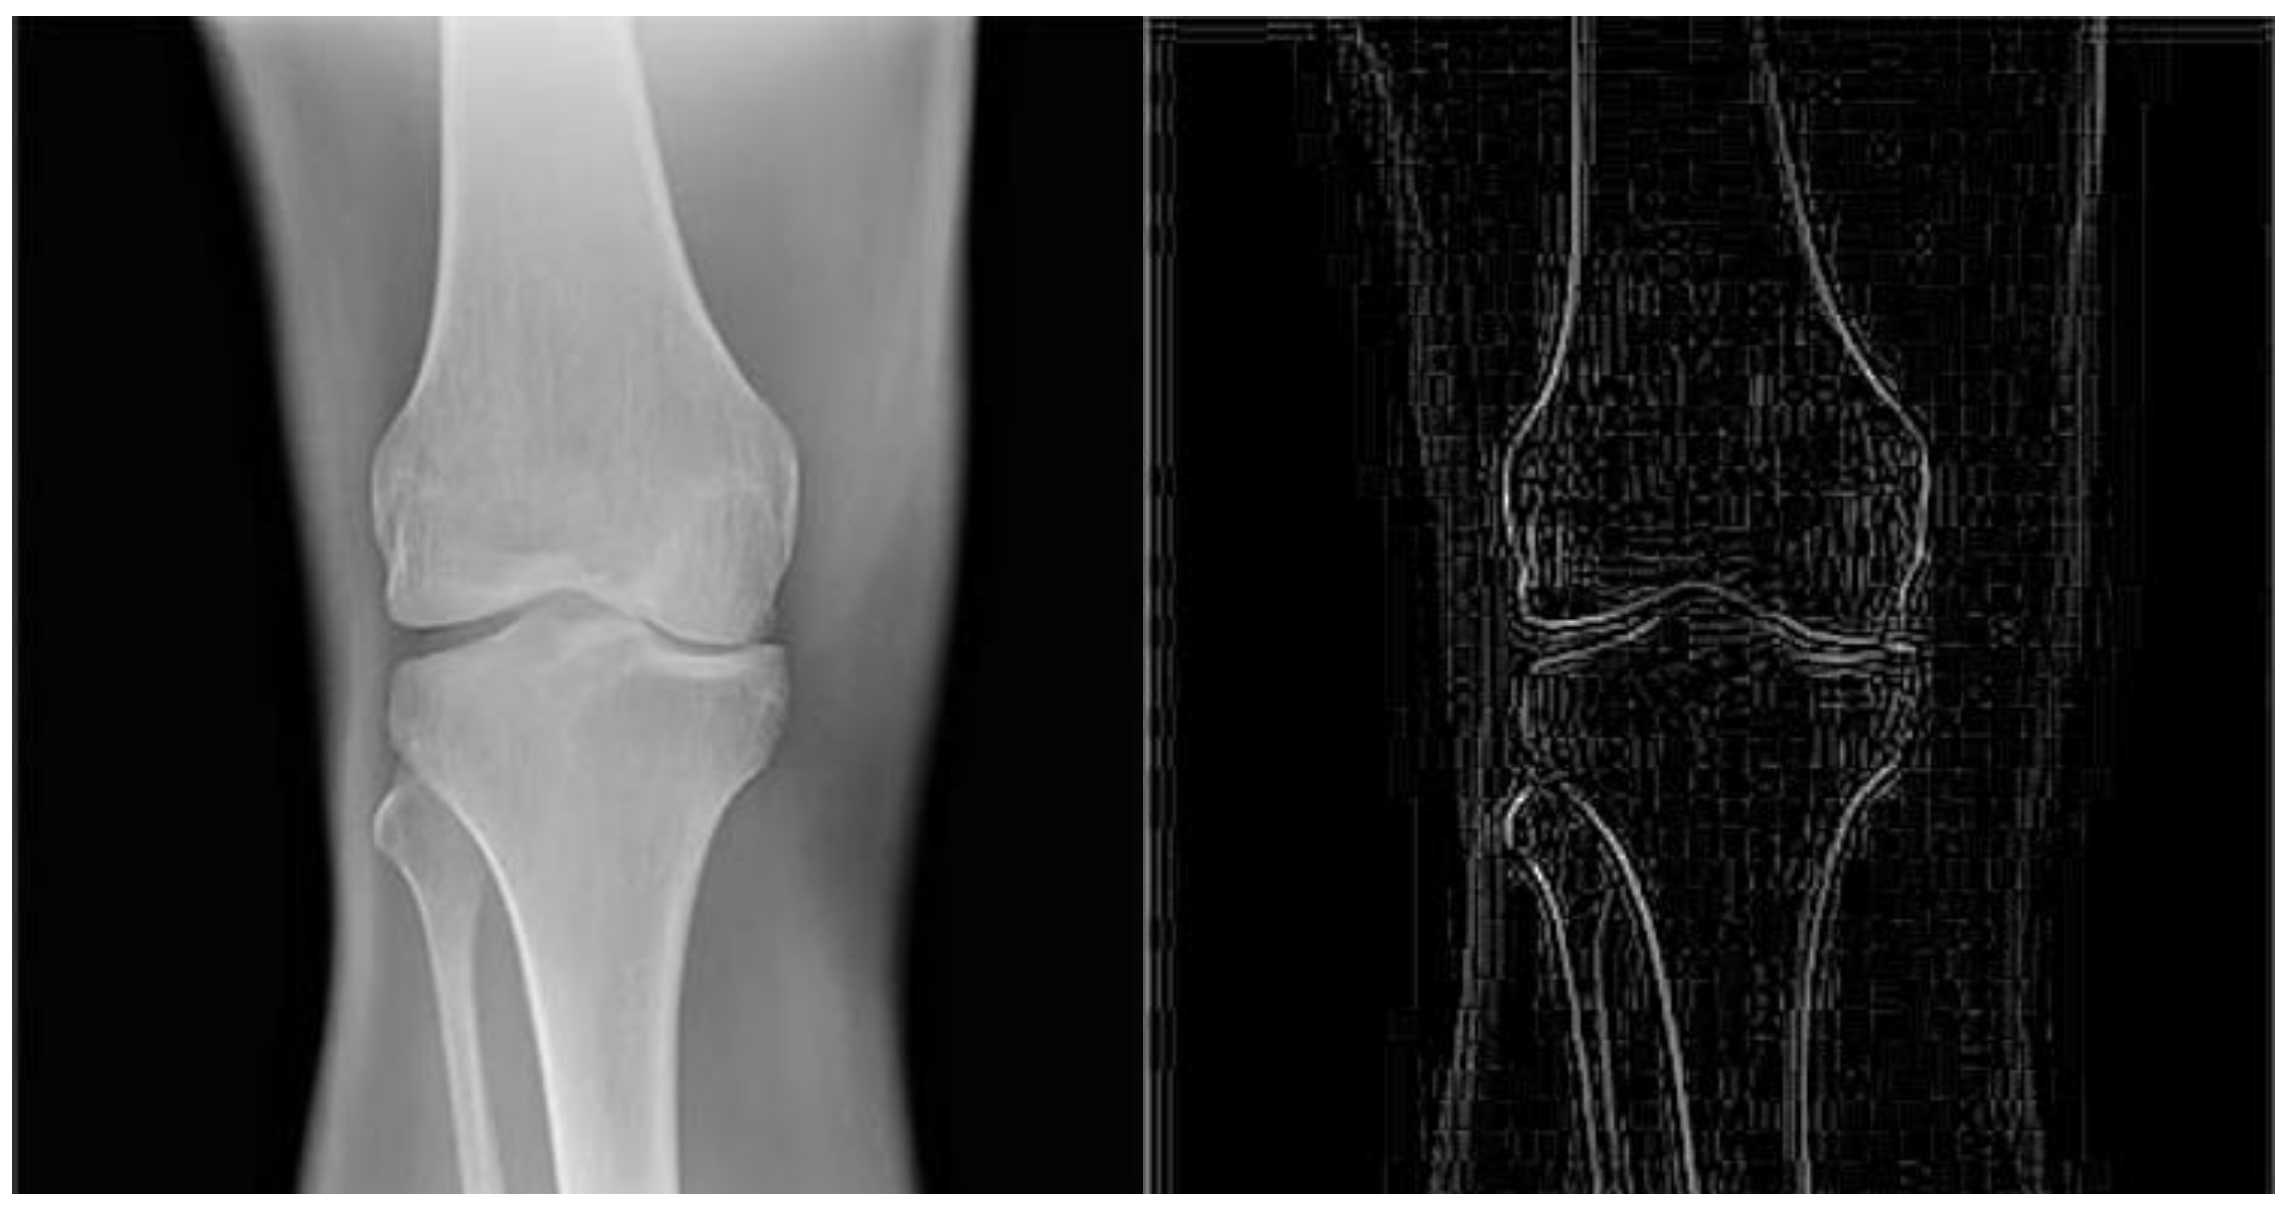

Figure 3.

The image on the right side is the result obtained by applying an edge detecting convolution filter on the image on the left side. The structure of the filter is showed in Figure 2.